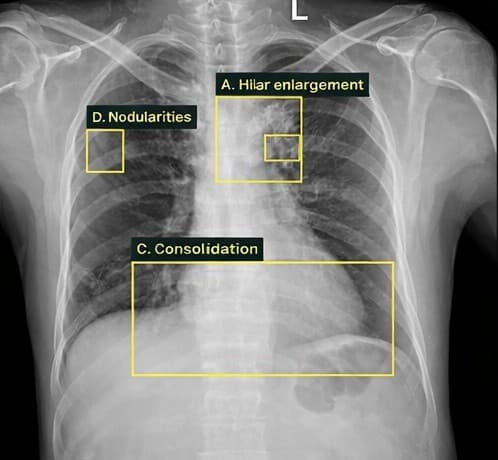

Tuberculosis

Tuberculosis | 0.94Sputum collection pending